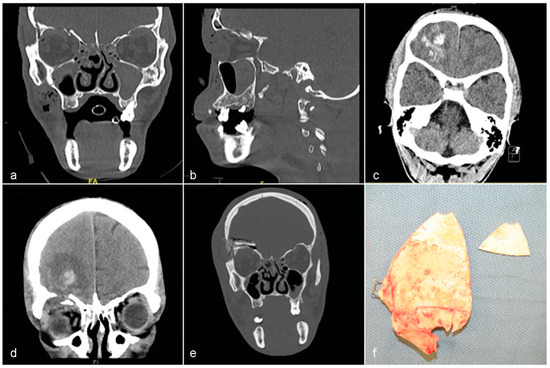

Case 2